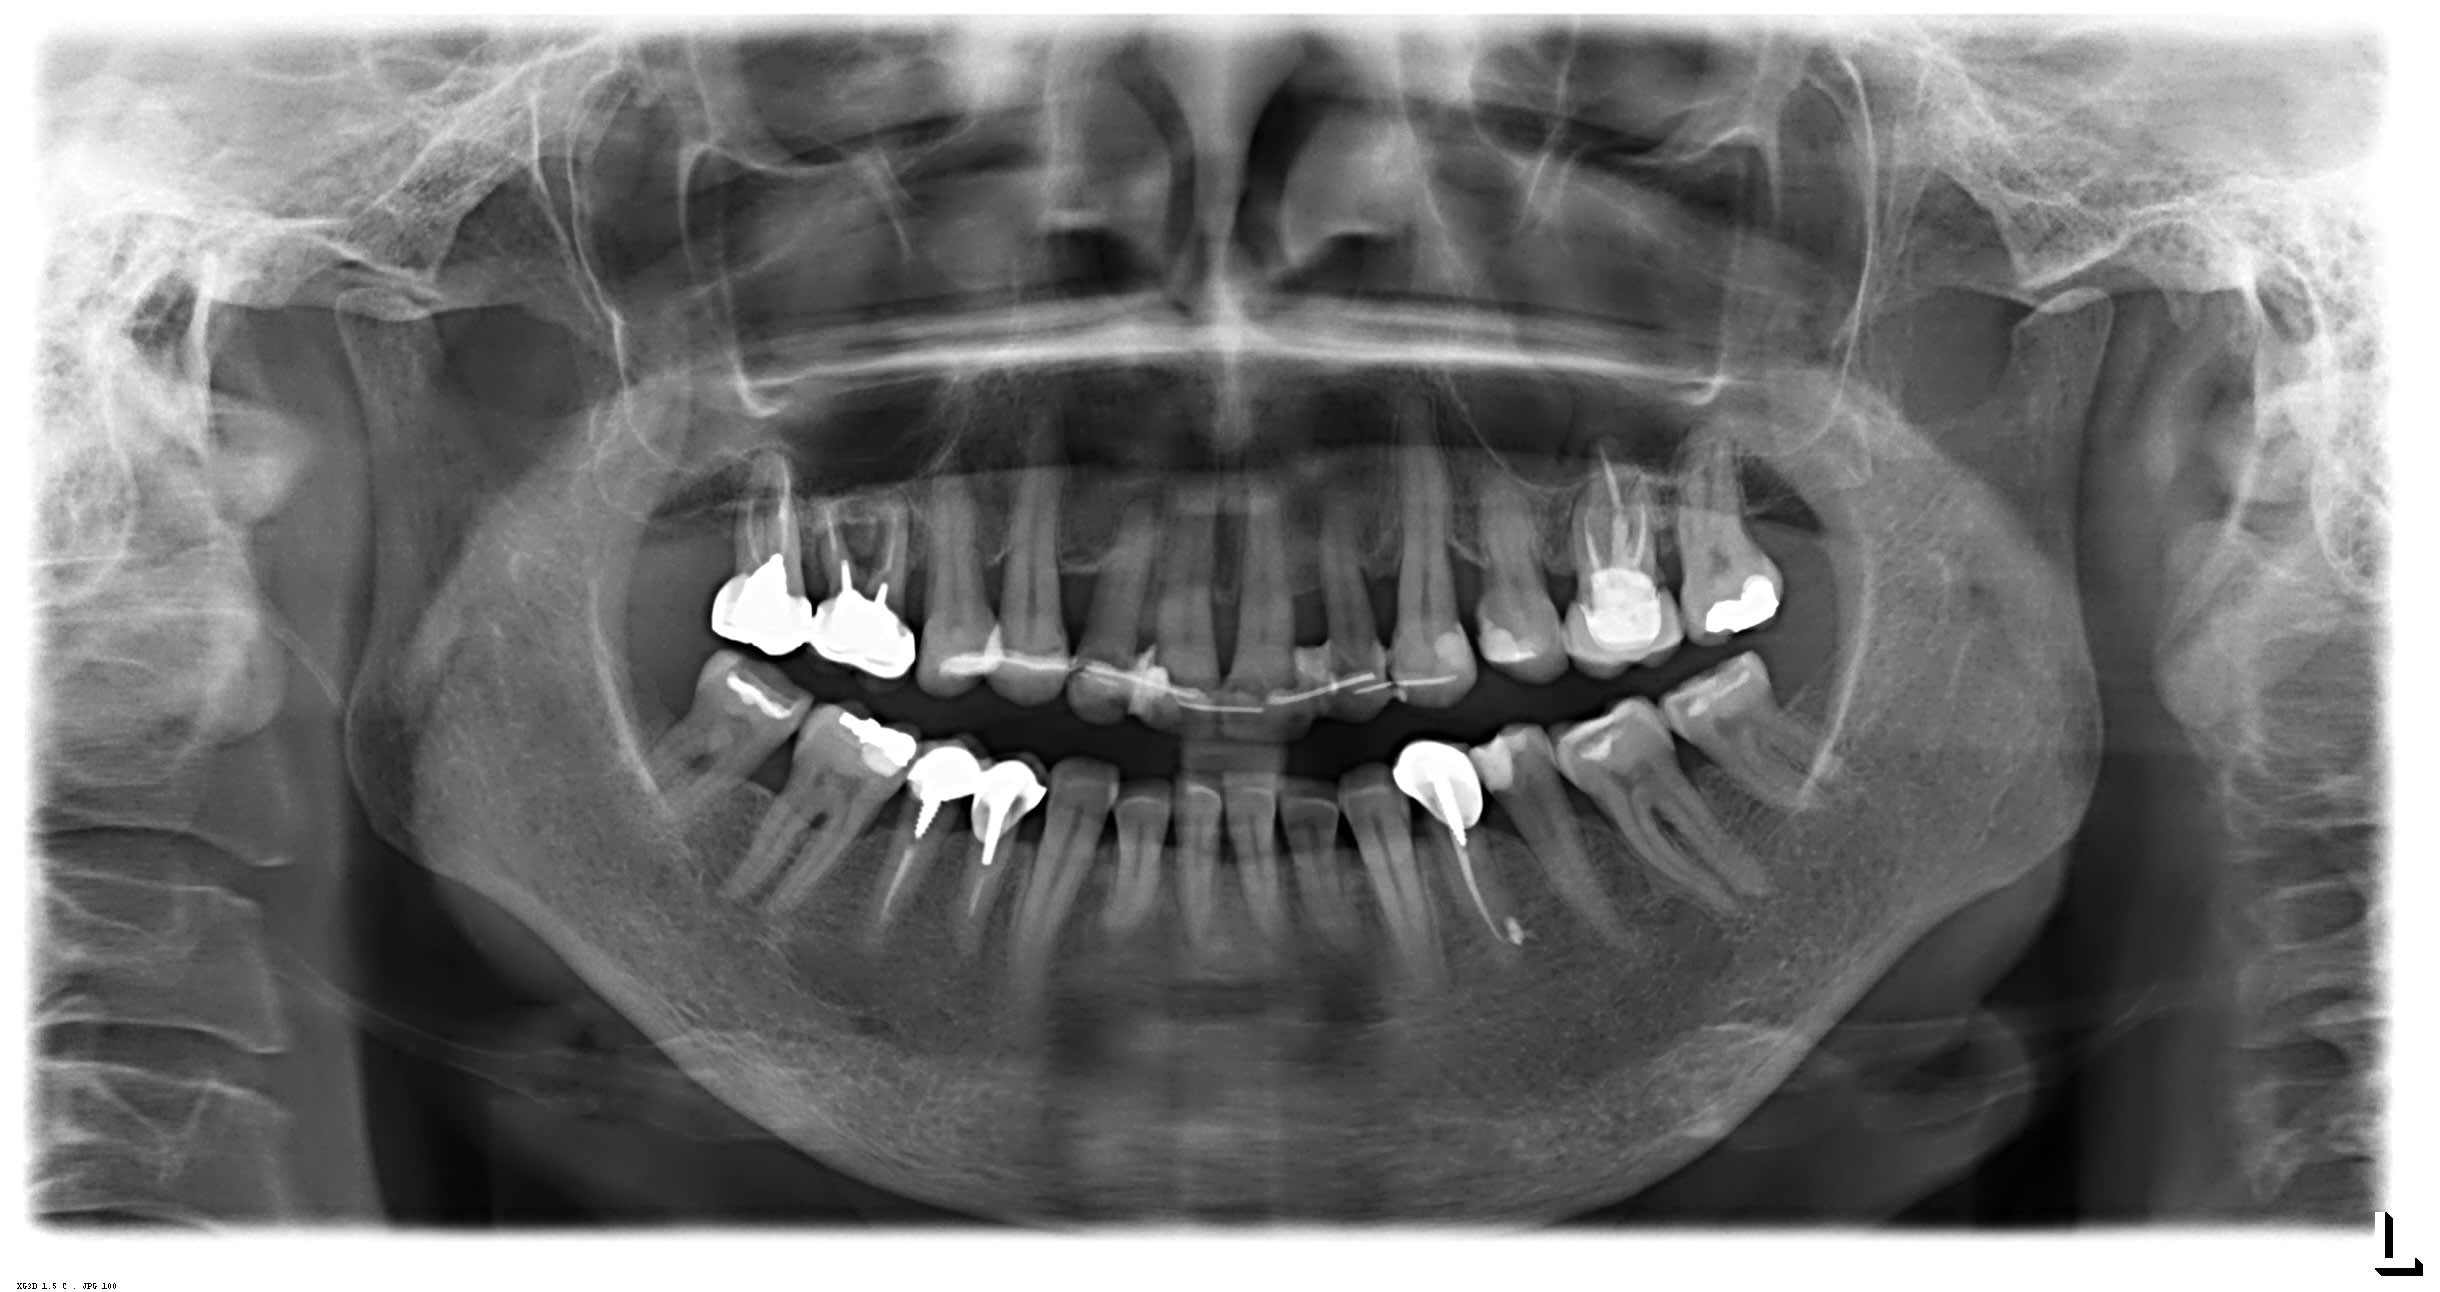

T’as pas lésion osseuse angulaire , sur les Canines notamment ? Et ça saigne pas en bas , sur ? Vas y mollo , ça m’a l’air stable du tout la paro , vu d’ici..

Faudrait songer à extraire la 16 aussi

Je veux bien me faire pendre si en M et D des incisives supérieures on a pas de poches.

Et enfin y a un diastème de 5 mm entre 21 et 22. Ce qui veut dire que sur les futures couronnes il y aura des couronnes plus larges à gauche qu’ à droite.

Je me disais bien sur la photo , y a comme qui dirait un souci. Ce sont en fait les 4 qu’ils ont virées... ce qui expliquerait le bloc antérieur trop rentré. J’avais pas assez regardé la pano. Et même en rentrant tout ça, y a des diastemes pas uniquement imputables à la paro

Tu as une alvéolyse périphérique de presque 50%, associée à des lésions infra osseuses, dont au moins une majeure en palatin de 12, tout cela n'étant masqué que parce que le biotype parodontal est favorable. Ce n'est pas grave, si le boulot est bien fait elle pourra le mener au bout, mais à moins d'avancées majeures en paro dont je n'ai pas eu connaissance, on ne fait pas encore repousser l'os, et quand on a de la gencive à 5mm au-dessus du niveau osseux, ça s'appelle une poche.

il y a 1 truc qui est étonnant , ç est qu'il n'y a pas de fil de fer en bas .

j'en déduis que l'ortho n'y a pas touché .

s'il n'y a pas touché , ç est qu'il n 'y avait qu'1 pb esthétique à ces yeux , il y a 20 ans , .

je ne vois comme point de départ qu'une béance avec dysfonction linguale .

j'en déduis donc que le haut ne peut être en bonne occlusion avec le bas s'il n'y a pas touché .

je ne pense pas qu'il y avait un un pb paro majeur à l'époque , sinon , il ne se serait pas lancé dans ce délire .

en tout cas , il a du le regretter au vu des nombreux bricolages de fil de fer pour essayer de maintenir les dents du haut .

1 femme , motivée pour accepter ce ttt ,et qui n'a pas de pb paro à 40 ans ne déclenche pas une maladie parodontale subitement .

ç est donc qu'il y a eu une réponse tissulaire à 1 gros pb d'occlusion + 1 grosse interposition linguale de compensation ( on remarquera les inc inf latérales rikiki ) .

Comment une chirurgie réparatrice peut elle réparer un effet iatrogène si l'on en supprime pas la cause ?